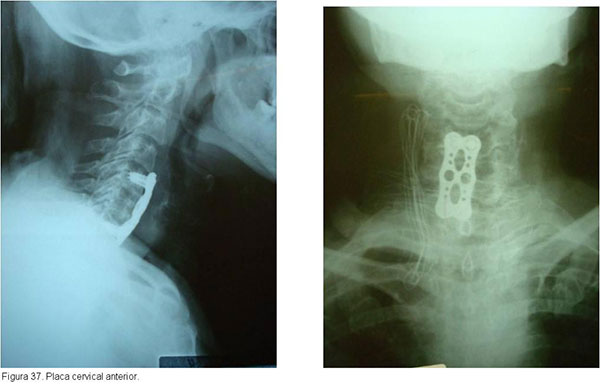

As fraturas cirúgicas da região cervical são estabilizadas com amarrilhos, placas e parafusos, sempre associados à enxertia óssea para facilitar a artrodese. O uso de estabilização anterior e/ou posterior depende do tipo de fratura.(figuras 37, 38, 39)